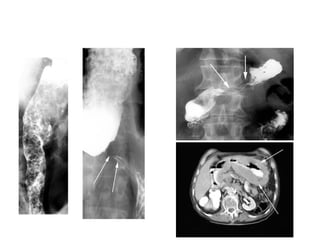

CARCINOMA

dạng polyp / dạng chồi sùi

dạng ổ loét – các nếp niêm mạc

dạng nhiễm cứng - linitis plastica

K dạ dày – khuyết hình lõi táo

K dạ dày dạng polyp

K dạ dày – hình ống nước do nhiễm cứng thành

Linitis plastica

K dạ dày dạng loét